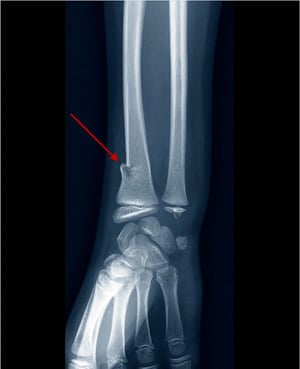

Frattura del toro del polso

Questa frattura del toro del radio distale è visibile solo come una leggera irregolarità della corticale ossea.

LIVING ART ENTERPRISES, LLC/SCIENCE PHOTO LIBRARY

Frattura a legno verde del radio distale

Questa radiografia mostra una frattura a legno verde del radio distale, visibile come discontinuità nella parte radiale della corticale (freccia).

Questa radiografia mostra una frattura a legno verde del radio distale, visibile come discontinuità nella parte radial

... maggiori informazioni

ZEPHYR/SCIENCE PHOTO LIBRARY